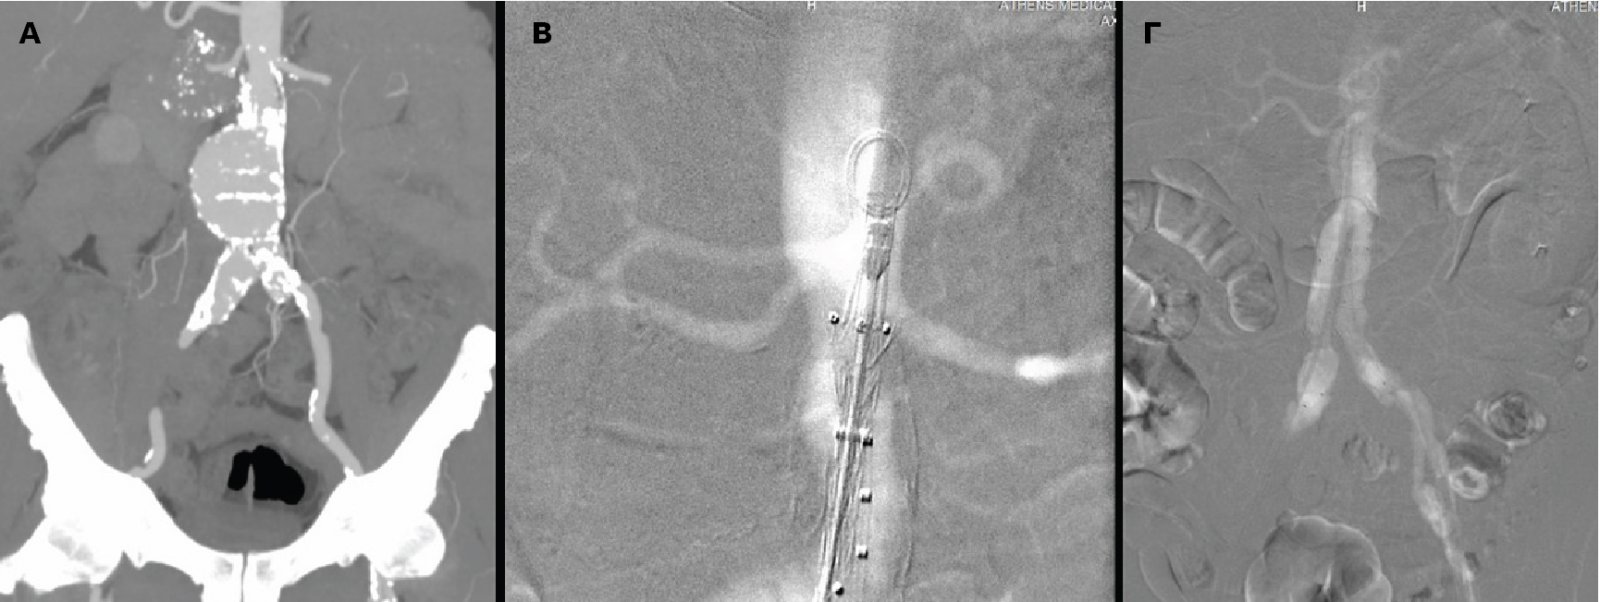

Με επιτυχία πραγματοποιήθηκε, για πρώτη φορά στην Ελλάδα, στο Ιατρικό Κέντρο Αθηνών, η διαδερμική ενδαγγειακή αποκατάσταση κοιλιακού ανευρύσματος μόνο με τη χρήση διοξειδίου του άνθρακα (CO2) και χωρίς καθόλου ιωδιούχο σκιαγραφικό.

Αξίζει να σημειωθεί ότι η ποιότητα της αγγειογραφίας ήταν ισάξια με αυτήν του ιωδιούχου σκιαγραφικού, τα μοσχεύματα τοποθετήθηκαν με απόλυτη επιτυχία αποκλείοντας το ανεύρυσμα και η νεφρική λειτουργία του νεφροπαθούς ασθενούς δεν επηρεάστηκε καθόλου.